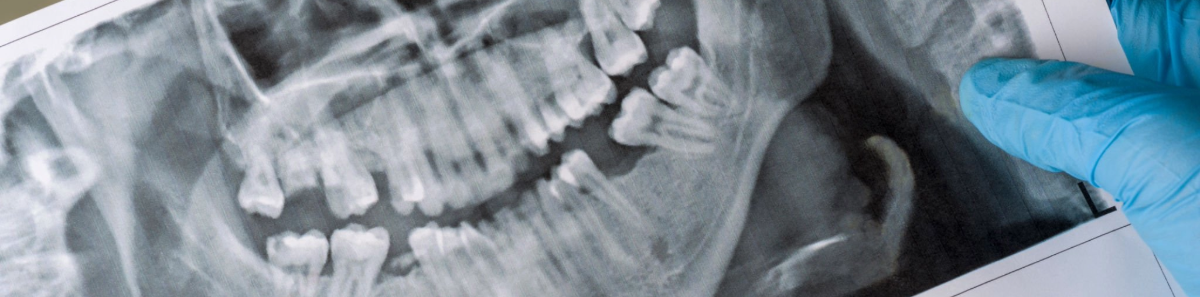

Extracción terceros molares

Es posible que se haya preguntado por qué tenemos que quitarnos las muelas del juicio. La razón principal tiene que ver con la falta de espacio para estos dientes. Para cuando las muelas del juicio crecen, la mayoría de los adultos ya tienen todos los dientes erupcionados y no queda mucho espacio en el arco dental para permitir 4 dientes más y que crezcan en una posición y alineación saludable.

Además cuando los terceros molares comienzan a erupcionar pueden ser bloqueadas por los segundos molares o por el hueso de la mandíbula que se encuentra por encima de las muelas del juicio. Cuando estas muelas en erupción se topan con estas barreras, quedan atrapadas en una posición incómoda, a veces referidas como «molares retenidos».